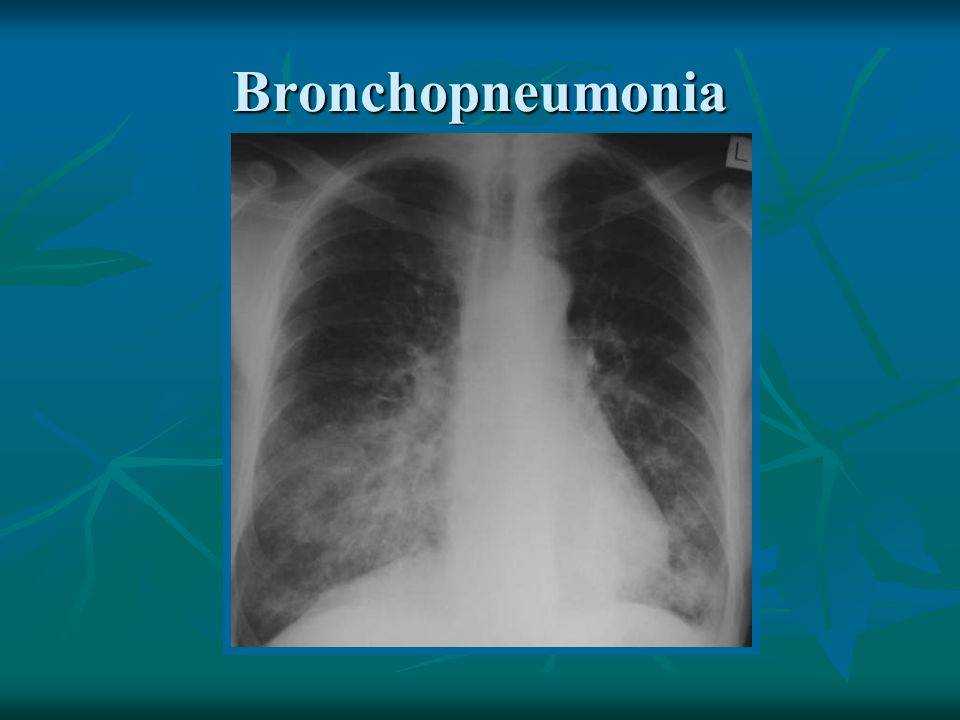

Рентгенодиагностика бронхопневмонии: Советы и примеры

Раздел: Альбом открытий